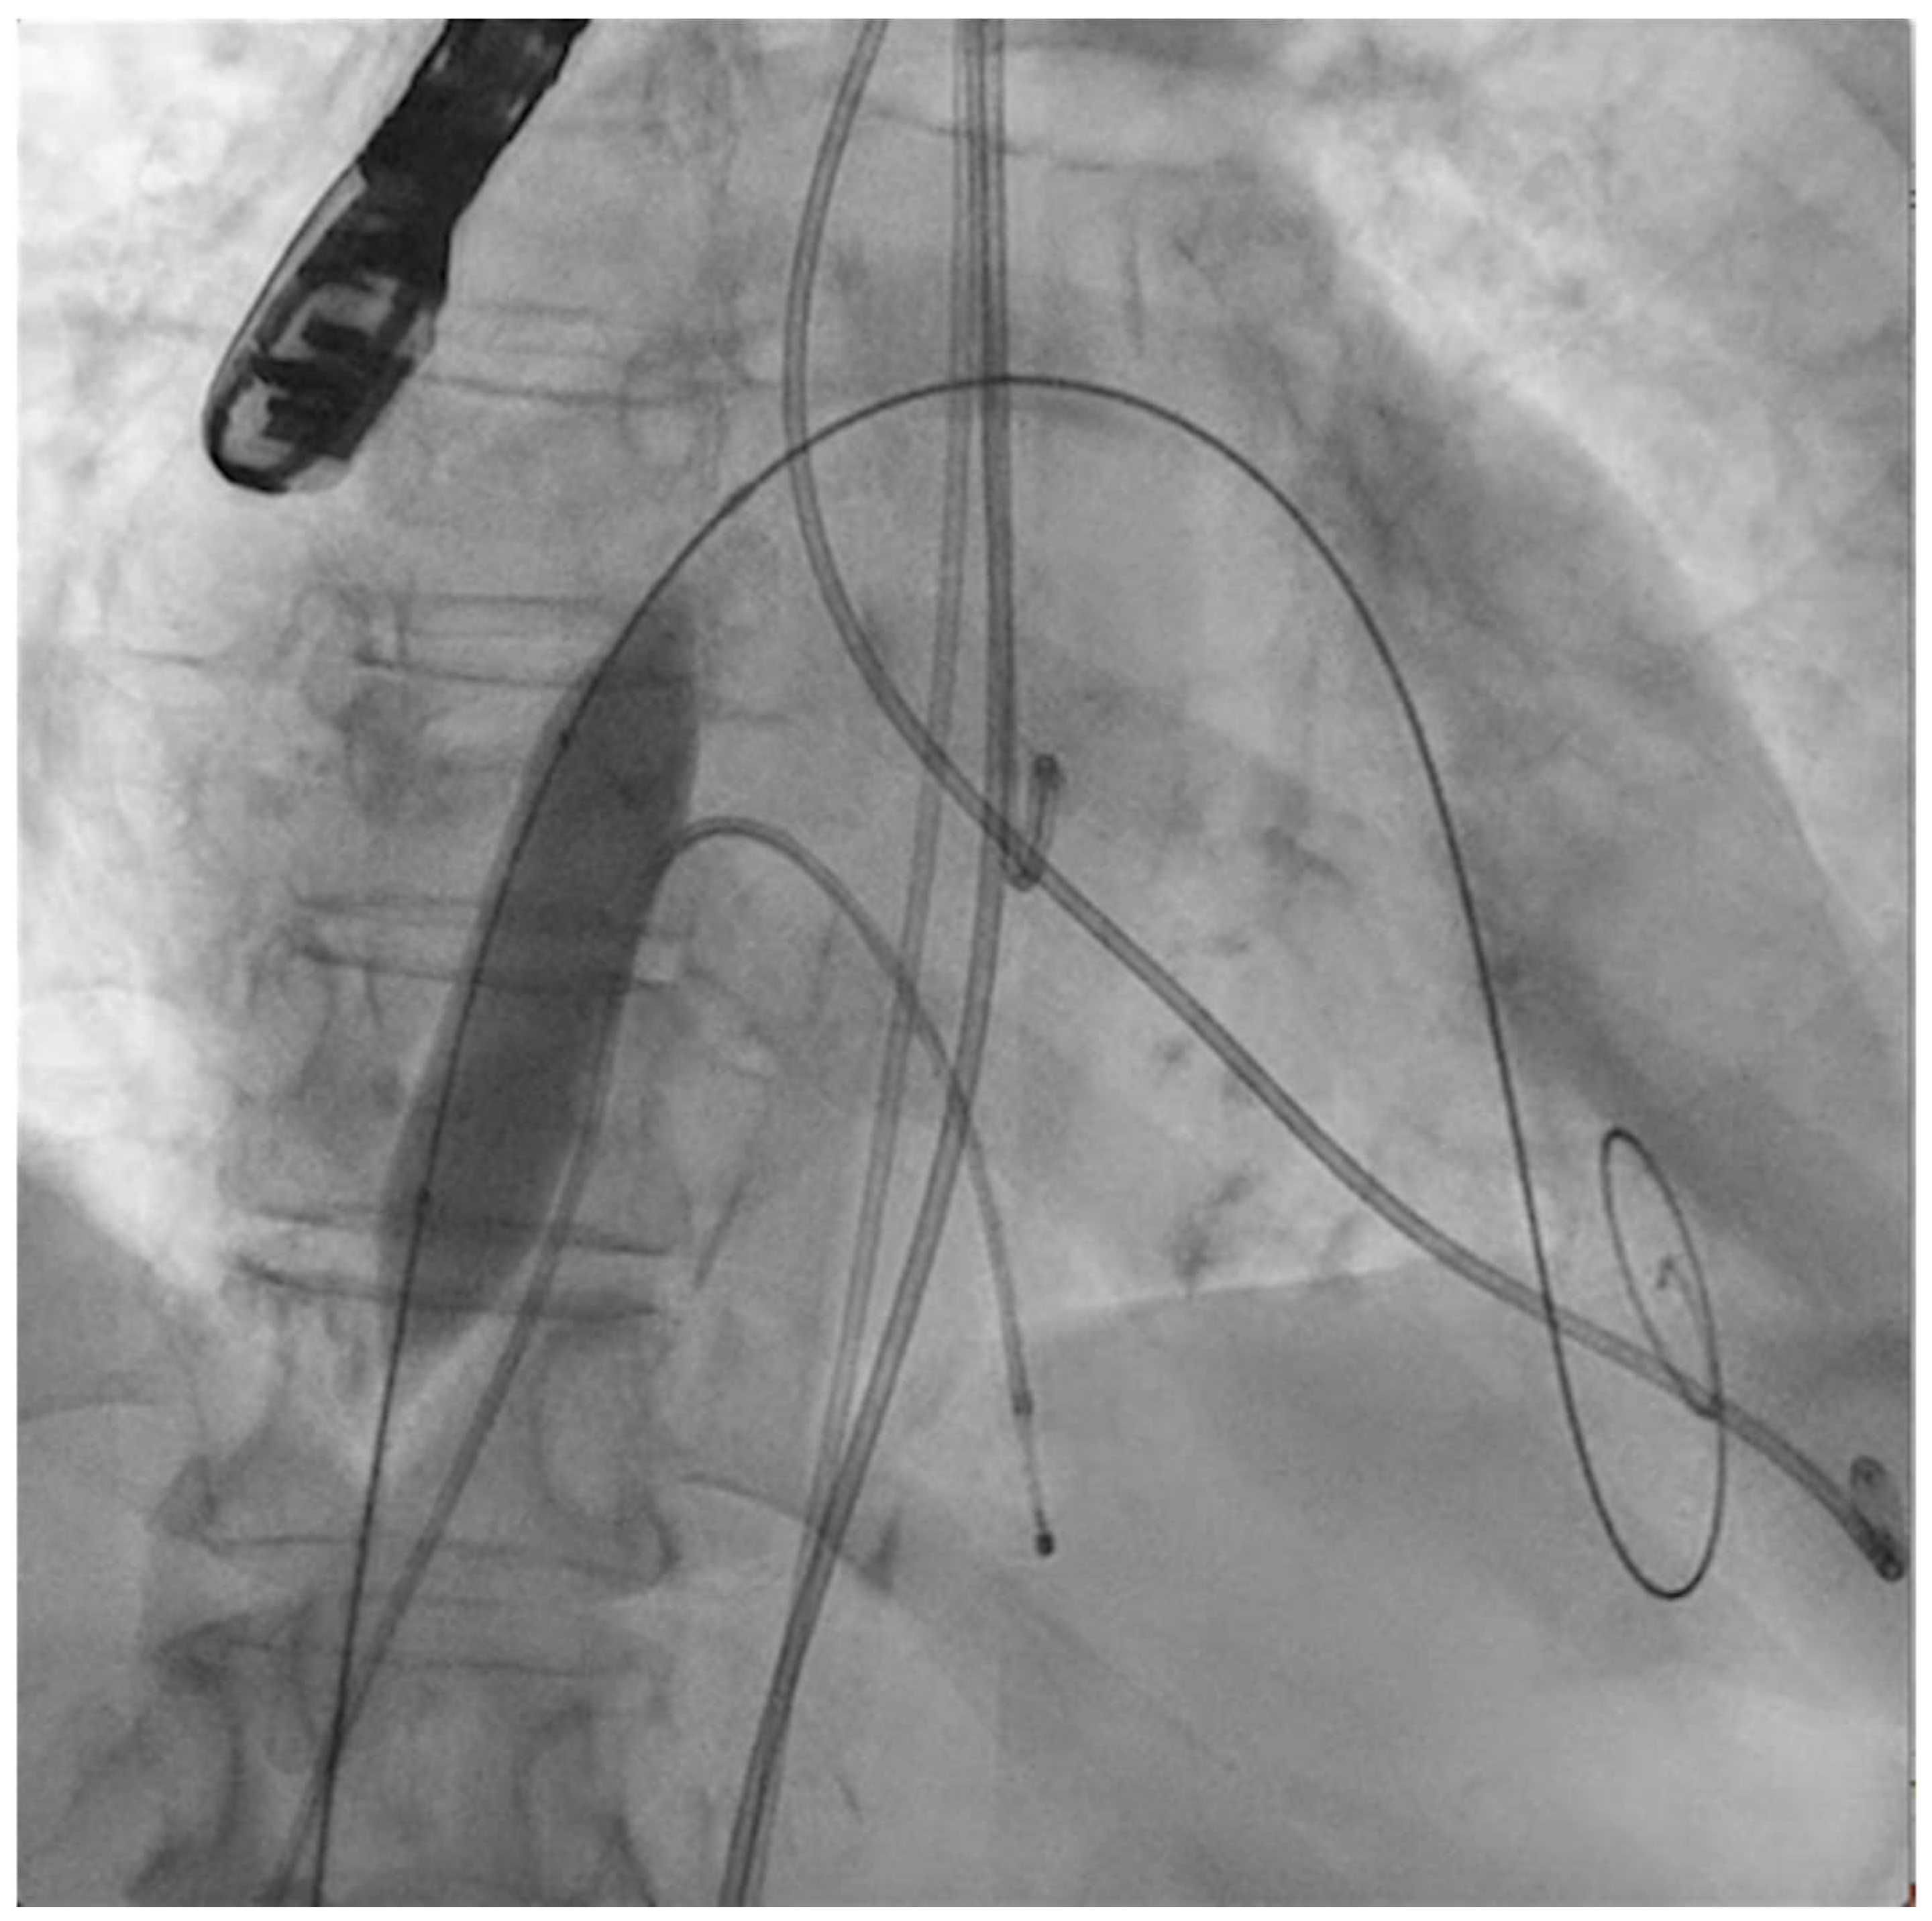

The next steps consist of crossing the mitral valve with three long high-support 0.014´´ wires downstream into the left ventricle (LV) (Figure 2) and then advancing three lithotripsy balloons (Shockwave Medical) across the mitral valve; with rapid pacing (120 beats/min), simultaneous inflations of all balloons will deliver a total of 90 pulses from each balloon (Figure 3). Finally, access to the LV has to be attained again with the Safari wire to complete PMC with large balloons appropriately sized to the mitral valve area and diameters (Figure 4). Embolic protection devices are encouraged to avoid neurological or systemic ischemic events due to calcific debris.

Figure 2.

Three angioplasty wires crossing the mitral valve into the left ventricle.